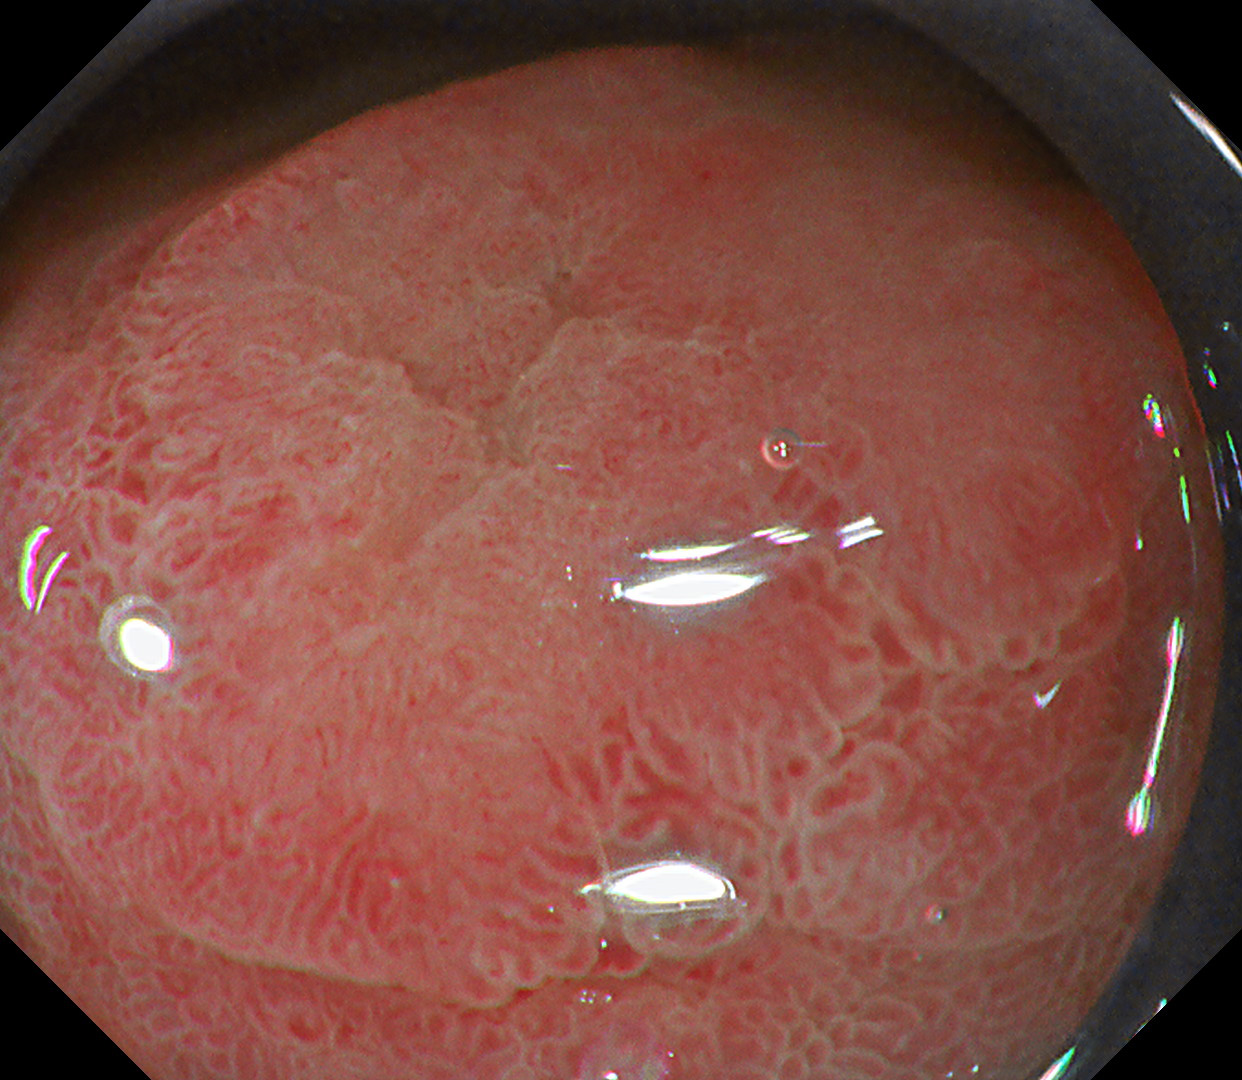

4. WLI

#WLI #A3 structure enhancement

Single nodular lesion seen at antrum with elevated edges and indistinct margins. The demarcation line is not clearly visible in WLI.